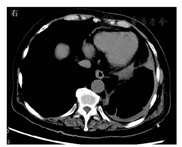

患者女,63岁,因"胸闷、发热1周"于威海市中心医院就诊,体温最高达38.5 ℃,血常规检查白细胞计数和中性粒细胞比例升高,考虑细菌感染,给予头孢克肟0.1 g(2次/d)口服抗感染治疗,服药1周后仍然高热不退,复查白细胞计数、中性粒细胞比例和CRP水平均升高,为查明病因于2019年1月10日收住入院,患者既往有多年的糖尿病和高血压病史。入院体格检查:体温为38.2 ℃,心率为130次/min,呼吸为20次/min,血压为151/79 mmHg(1 mmHg=0.133 kPa);神志清,全身浅表淋巴结未触及肿大;心律齐,各瓣膜听诊区未闻及杂音;双肺呼吸音粗,可闻及干啰音;腹软,无压痛、反跳痛,肝脾未触及,肠鸣音正常,双下肢无水肿。实验室检查:白细胞计数为28.19×109/L,中性粒细胞比例为0.96,血红蛋白为108 g/L,血小板计数为152×109/L,超敏CRP为213.7 mg/L,降钙素原为6.36 μg/L;pH值为7.45,氧分压为52.2 mmHg,二氧化碳分压为35 mmHg;AST为32 U/L,ALT为32 U/L,葡萄糖为16.9 mmol/L,总钙为2.05 mmol/L,钾为4.2 mmol/L,钠为111 mmol/L,氯为89.7 mmol/L;PT为13.9 s,纤维蛋白原为4.06 g/L,D-二聚体为4.55 mg/L。胸部CT检查示:左侧胸腔积液合并左肺膨胀不全,内见多发气体影(图1)。胸部多普勒超声检查示左侧有大量胸腔积液。为明确胸腔积液性质,并使肺复张,行胸腔闭式引流,引流液为脓性。胸腔积液常规检查示:黄色浑浊,比重为1.029,李凡他试验呈阳性,白细胞计数为93.2×109/L,中性粒细胞比例为0.92,单核细胞比例为0.08,考虑为炎性渗液。胸腔积液生物化学检查示:葡萄糖水平降低,为0.11 mmol/L,提示严重细菌感染。血培养、胸腔积液培养均显示嗜沫凝聚杆菌,为细小革兰阴性杆菌(图2)。分别接种于血平板和巧克力平板,在体积分数为0.05的二氧化碳(CO2)条件下培养72 h后有菌落生长,呈灰白色、形态细小,不溶血;在中国兰平板上无细菌生长,推测该菌为苛养菌。经德国布鲁克质谱仪鉴定及16S rRNA测序,结果均为嗜沫凝聚杆菌,且对头孢曲松、左氧氟沙星、阿米卡星、美罗培南等抗菌药物敏感。患者入院后给予哌拉西林他唑巴坦4.5 g,每8 h 1次抗感染治疗3 d,明确病原后,调整为头孢曲松(2.0 g,1次/d)联合左氧氟沙星(0.6 g,1次/d)静脉滴注,并继续行胸腔闭式引流。治疗2周后,患者双侧肺部干啰音减轻,胸闷、憋气症状较前有所改善。实验室检查示白细胞计数、CRP和降钙素原水平有所下降,抗感染治疗有效。但患者仍反复发热,胸腔脓液引流不佳,出现血流感染,经家属同意后行胸腔镜下胸膜粘连松解术,同时完善腹部超声检查,以排除其他脏器脓肿可能。应用美罗培南1.0 g(每8 h 1次)联合依替米星0.3 g(1次/d)继续抗感染治疗。胸腔镜术中诊断为左侧脓胸,患者术后无发热,胸闷、憋气症状明显改善,继续抗感染治疗2周后复查胸部CT示肺部炎症及脓液吸收较前好转(图3)。患者无发热、胸闷、憋气,双肺仅闻及少量啰音,暂停美罗培南,给予口服环丙沙星(0.5 g,2次/d)巩固治疗2周,并做好出院指导。

注:黑色箭头所指为嗜沫凝聚杆菌的形态